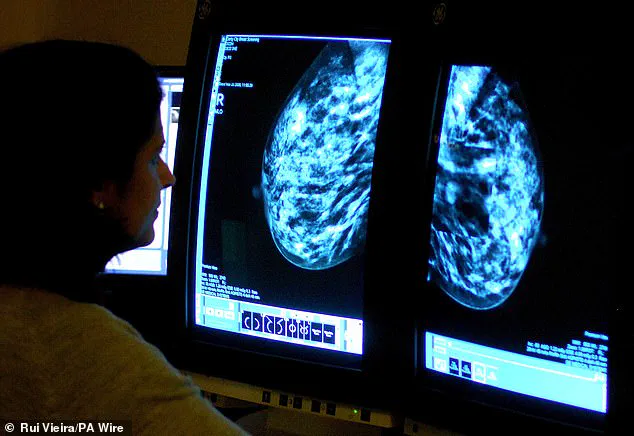

Ramsey stressed. 'In fact, screening may be the only way some women get their breast cancer detected.' Dense breast tissue, a factor that complicates early diagnosis, was another critical point raised by the surgeon. 'Dense breast tissue makes breast cancer harder to detect.

It’s common and normal, but it may require additional imaging.

Ask if your breast density is noted on your mammogram,' Dr.

Ramsey advised.

Research has increasingly shown there is a clear danger associated with having dense breast tissue—well over a million women in the UK are at a heightened risk of cancer as a result.

Density is not something you can feel or spot; it requires a mammogram, a fact that underscores the importance of regular screenings and open dialogue with healthcare providers.

The current national breast cancer screening programme in the UK, which invites women aged 50 to 70 for mammograms every three years, has come under scrutiny for a critical oversight: the failure to inform women about the density of their breast tissue.

Despite the fact that dense breast tissue can obscure cancer detection in standard mammograms, many women are left unaware of this characteristic, even as it may influence their risk profile and the effectiveness of their screening.